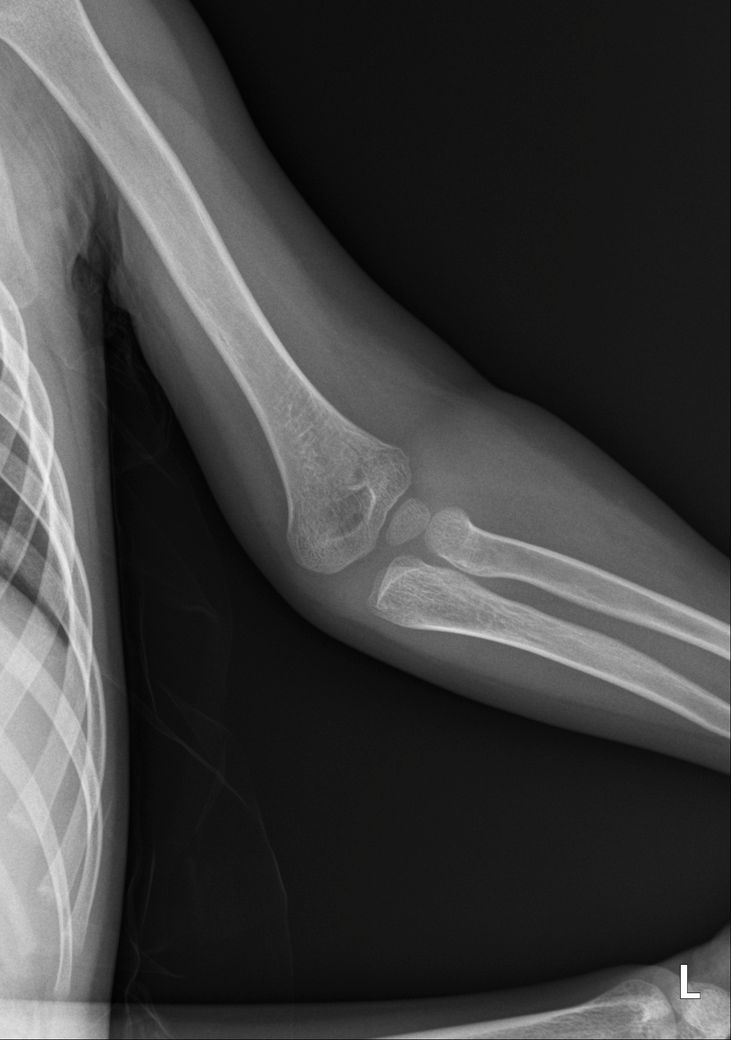

소아팔꿈치골절 씨티나 엠알아이 찍어 봐야할까요?

안녕하세요 엑스레이상 골절 확인되었는데 사고시 팔이 꺾여 아빠가 팔을 돌렸다고 해요 성장판 인대 근육도 걱정이 되는데 씨티나 엠알아이 검사를 추가로 해야할까요?

병원에서는 씨티는 권유하시는데 방사능이 걱정되어 고민중입니다 일요일 다쳤고 월요일 병원 진료 후 통깁스중입니다 성장판 쪽은 아니라고 하시던데 성장판 괜찮을까요?

• 3번 째 사진